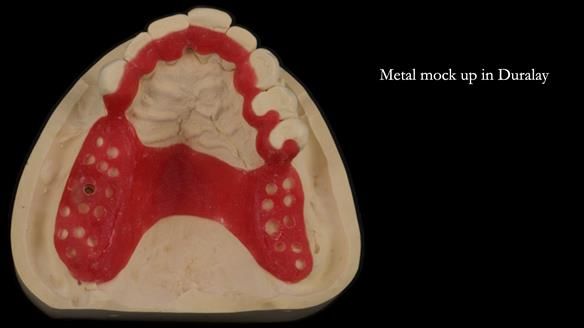

Instead, we made a Scandinavian-style, metal-based lower RPD.

It’s worth saying that the lower denture in this case was made in the early days of Rowan and me using the Scandinavian approach. Rowan cast the metalwork himself for this denture.

Looking back, we would make this denture more hygienic now. The design and finish would be more refined and delicate, particularly when compared with the upper metalwork, which was made later using Chris Hesketh’s chrome work. I will discuss this in detail at the study club.

That said, the lower denture worked beautifully. It did exactly what it was meant to do, even though, by today’s standards, it looks a little agricultural.

A metal-based upper RPD was made,

with metal backings incorporated to future-proof the design

should further teeth fail.